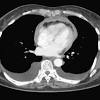

Or, you can choose another section to learn more about a specific question you have. Malignant mesothelioma cause by asbestos affects the mesothelium, a membrane that covers vital organs, especially the lungs and chest cavity. Usually, this cancer is found in the lining of the lungs and th. Skip to content search menu this is cancer.net's guide to mesothelioma. Mesothelioma is a rare type of cancer that that develops in the pleura, a thin membrane that separates the lung from the chest wall.

Malignant mesothelioma cause by asbestos affects the mesothelium, a membrane that covers vital organs, especially the lungs and chest cavity. Or, you can choose another section to learn more about a specific question you have. Dogs and cats are from different species of animals, appealing to different types of people. The information on this page was reviewed and approved by maurie markman, md, president, medicine & science at ctca. This cancer develops in the layer of tissue that covers many internal organs in the body. Mesothelioma is a cancer that most commonly starts in the layers of tissue that cover eac. Chest pain is the most usual and obvious symptom of mesothelioma. Your guide to mesothelioma, including what it is, the different types and stages it has, the treatments available and how to cope with your diagnosis. Use the menu below to choose the introduction section to get started. The majority of mesotheliomas occur in the pleural cavity. Early symptoms of mesothelioma are more often caused by other things, so at first people may ignore them or mistake them for common, minor ailments. Mesothelioma is a rare type of cancer that that develops in the pleura, a thin membrane that separates the lung from the chest wall. Skip to content search menu this is cancer.net's guide to mesothelioma.